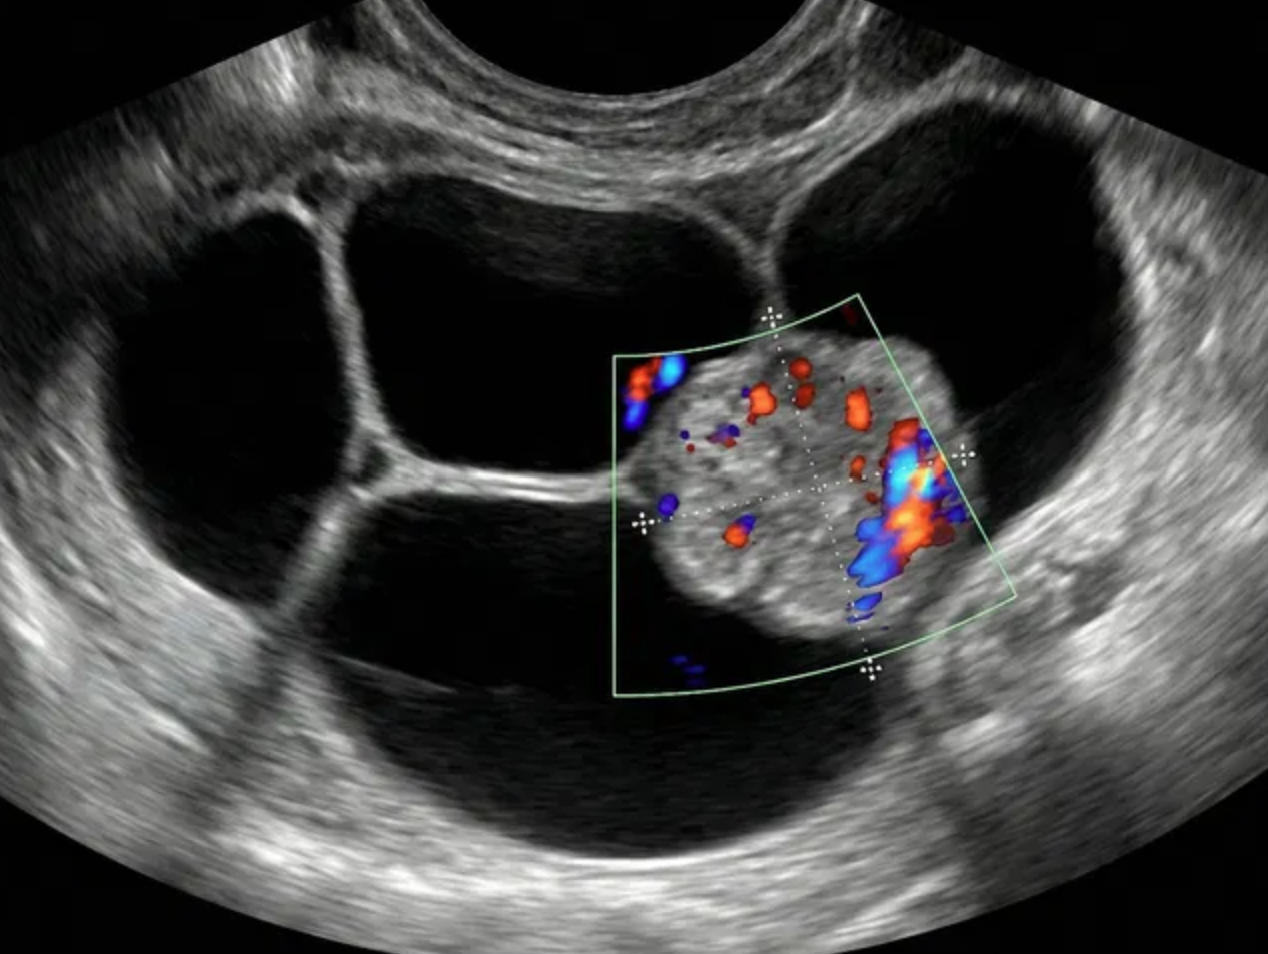

O-RADS US 5 — Alto Risco

Risco: ≥50%Cisto unilocular com ≥ 4 projeções papilares, cisto multilocular com componente sólido e IC = 3–4, lesão sólida com IC = 4 ou superfície irregular, presença de ascite e/ou nódulos peritoneais.

Achados ultrassonográficos

Conduta

Acompanhamento pelo gineco-oncologista